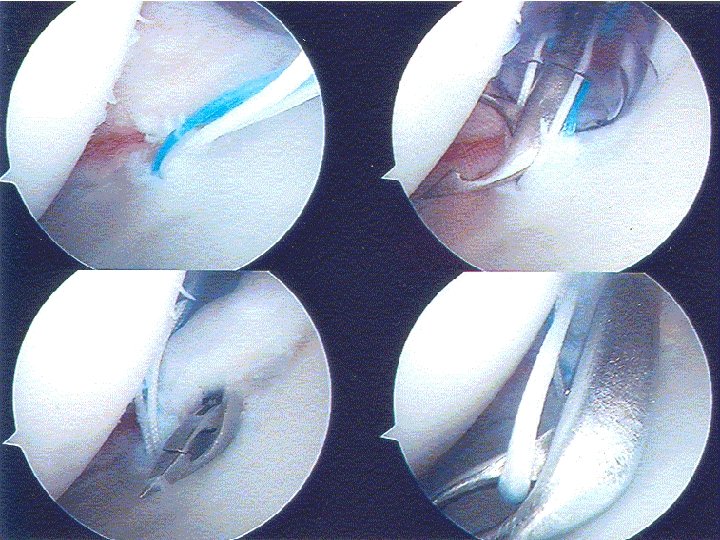

Acute Shoulder Dislocation Surgery Acute Repair of Anterior Labral Tear Einoder